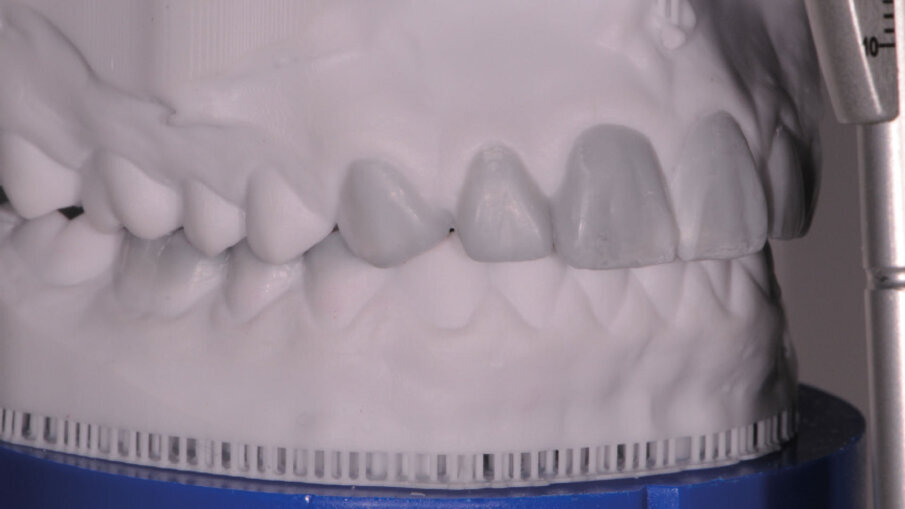

Alterazioni dell’anatomia inoltre si evidenziano anche a livello dei margini incisali dove sono evidenti delle micro fratture a carico dello smalto, originate da un probabile sovraccarico occlusale. Andando alla ricerca di una possibile causa di questo tipo di alterazione morfologica, un’attenta analisi dei gruppi posteriori evidenzia anche qui una situazione inusuale, cioè un’evidente riduzione dello smalto della porzione occlusale degli elementi diatorici specificamente dei premolari e dei primi molari, con conseguente alterazione dell’anatomia, mentre un normale sviluppo e una normale conformazione occlusale degli ultimi molari 37 e 47. Completando la visita e concludendo l’analisi con il V sestante si nota una inevitabile abrasione a carico dello smalto degli incisivi inferiori con usura dei canini soprattutto sul lato destro dove il canino in posizione 43 risulta riportare un’abrasione molto importante a differenza del 33 che appare normo conformato (Fig. 4). Emerge quindi che la situazione intra orale mostra alcuni elementi con alterazioni congenite come gli incisivi laterali e altri elementi con alterazioni acquisite di natura erosiva-abrasiva. In entrambi i casi il percorso da seguire è quello di, studiare le forme dentali residue per “reintegrarle” basandosi sugli elementi integri, utilizzati come guida per una riabilitazione “anatomicamente” guidata.

L’analisi dento labiale statica e dinamica e l’analisi fonetica sono state eseguite in una fase non operativa osservando i movimenti delle labbra durante una conversazione spontanea5, per questo motivo è determinante impostare da subito un rapporto cordiale e di fiducia con il paziente (Fig. 5). Queste analisi aiutano nella comunicazione attiva con il laboratorio odontotecnico6 che su queste indicazioni deve realizzare una ceratura diagnostica che interessi sia il gruppo frontale superiore che i gruppi diatorici inferiori (Figg. 6-7b). Sulla base della ceratura si preparano delle mascherine per stampare un mock up diagnostico7, 8, fondamentale per rivalutare intraoralmente tutti i parametri precedentemente analizzati tra cui i più rilevanti sono9: